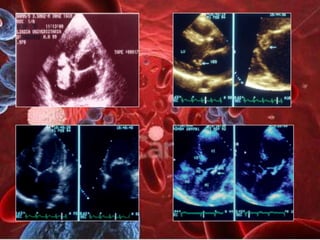

ENDOCARDITIS DE V.MITRAL        E.AGUDA V.AORTICA

SUBAGUDA POR EL        BISCÚSPIDE CONGENITA POR

STREPTOCOCCUS VIRIANS     EL STAPHILOCOCCUS AUREUS

INFLAMACION AGUDA      FOTOGRAFIA: ENDOCARDITIS

CELULAR Y FIBRINA          CURADA CON

PERFORACIOMES DE LA V.A.B

ENDOCARDITIS DE V.MITRAL E.AGUDA V.AORTICA SUBAGUDA POR EL BISCÚSPIDE CONGENITA POR STREPTOCOCCUS VIRIANS EL STAPHILOCOCCUS AUREUS INFLAMACION AGUDA FOTOGRAFIA: ENDOCARDITIS CELULAR Y FIBRINA CURADA CON PERFORACIOMES DE LA V.A.B